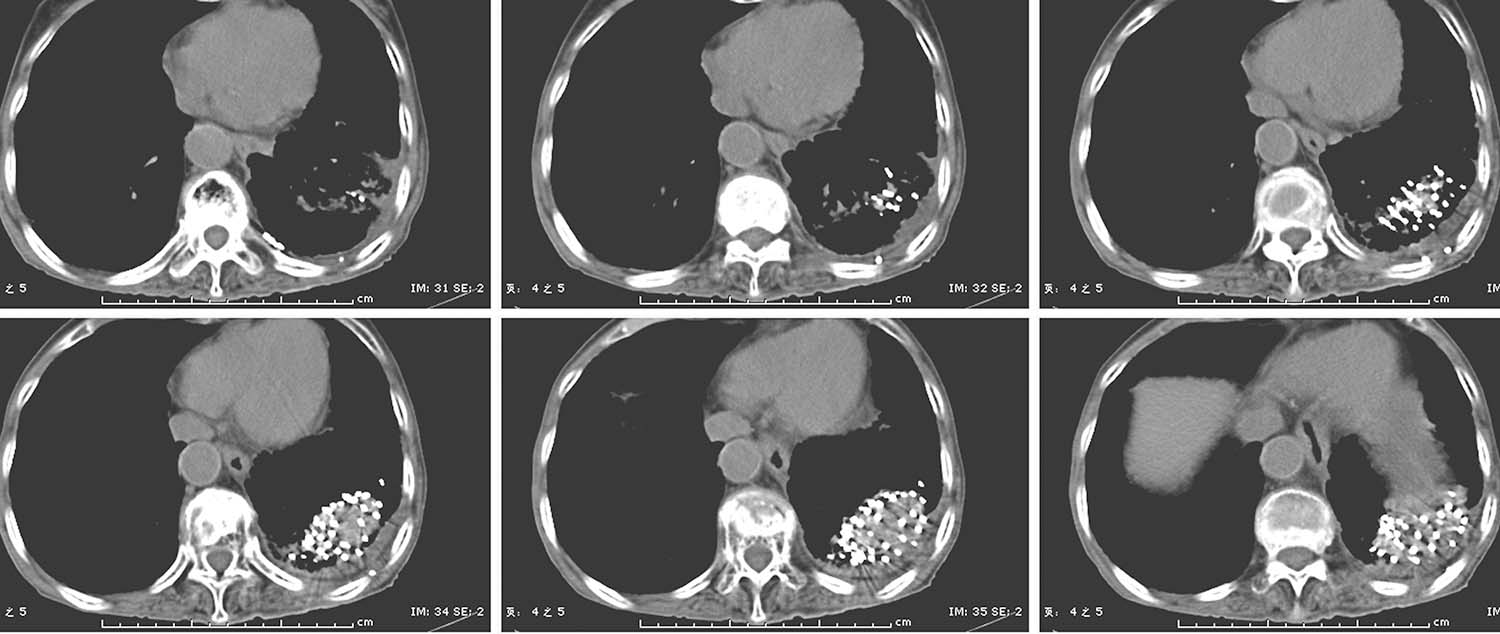

共面模板也称平面模板,是一种一次性成型的制式模板,按照0.5cm间距打孔,制作方法包括3D打印机打印、激光打孔及铸模法,可以制作成8.0cm ×8.0cm和10.0cm ×10.0cm等多种规格,由于模板表面有多个针道可以选择,应用时不需要复位。对于肺、肝等移动度较大的器官,可以先在肿瘤中心层面上植入2~3根固定针,使肿瘤与模板快速地“捆绑”在一起,使肿瘤所在的区域由“运动状态”变为“相对静止状态”,然后再按照术前计划依次进针,一定程度上解决了移动脏器布针不够准确的难题。

患者取与术前CT扫描相同体位,真空负压垫固定体位,防止穿刺过程中因体位变动给穿刺带来的不利影响。将导航支架与CT碳纤维床板相连接,以0.5cm层厚扫描,选取病灶中心层面,将一个预定进针点在皮肤表面做出大十字标记,消毒、铺巾、局麻,安装模板,用激光灯校准模板,使激光灯的 x 轴和 y 轴投影与模板表面的标记线相重合,利用数字化角度仪或者水平仪调整模板的角度和方向,使模板在 y 轴方向的角度为零,调整 x 轴方向的角度,与术前计划保持一致。选择病灶中心层面,参考术前计划,将数根穿刺针抵达皮肤表面,扫描观察针尾走行方向,再次校准模板,然后测量进针的深度,完成该层面的进针,如果是肺等移动度较大的脏器,可以先插入2~3根固定针,将病灶与模板迅速“绑定”(图4-3-1),然后再依次完成其他层面的进针,如果遇到坚韧骨骼遮挡,使用捻针或骨钻打孔技术破骨插植,待完成所有层面的进针以后再植入粒子。

测量各层面的进针深度,依据术前计划逐层植入粒子,在拔除穿刺针之前,再次行CT扫描,仔细观察粒子的分布情况,如果发现粒子聚拢或者移位,即刻进行补种。术毕即刻大范围扫描,进行术后剂量评估。

(1)避免了徒手穿刺的随意性,能够按照术前计划精确布针。

(2)能够保证同一层面和不同层面的多个穿刺针平行等距,实现术前计划与术后验证的吻合,特别对于大体积肿瘤更有优势。